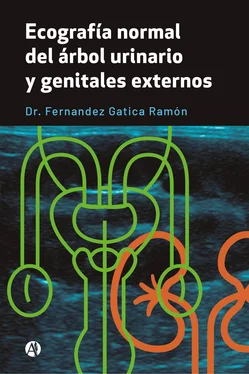

Fig: 7

Fig: 7, corte longitudinal a nivel de cabeza de epidídimo izquierdo, se puede ver: tabiques ecogénicos, regulares menores de 3. 0 mm.